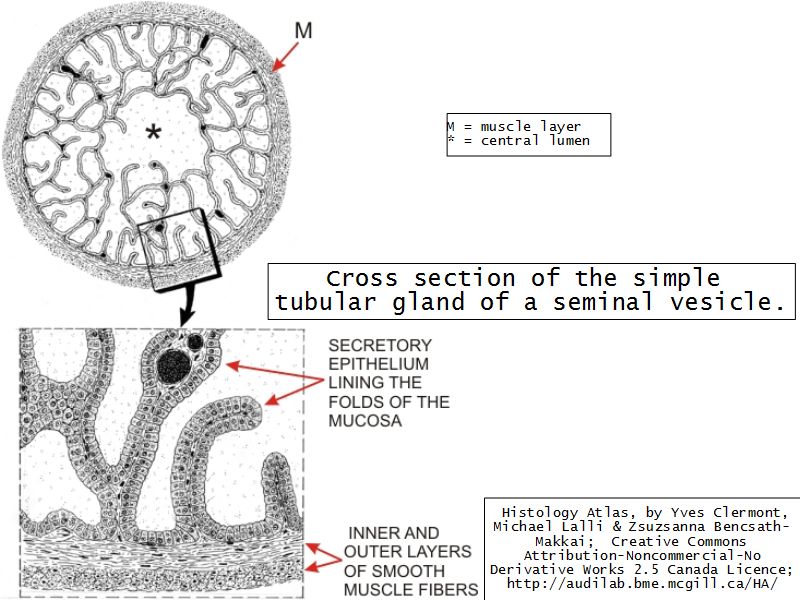

Vesicula seminalis

Slide 81Vesicula seminalis

- Mucosa

- Epithelium

- Lamina propria

- Muscle layer

Mucosa

- Lumen

- Irregular

- Store secretions

- Pseudostratified columnar epithelium

- Lamina propria

- Contains AVL

- Folded mucosa ^^ surface area

Muscle layer

- Inner circular

- Outer longitudinal